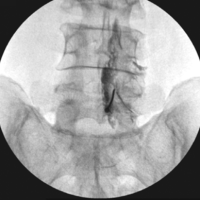

For instance, patients stabilized with terminal spinal metastatic disease may have a limited life span to achieve bony fusion. Moreover, their bone healing capacity is often compromised due to continuous chemoradiotherapy and poor nutritional status. For these reasons, the goals of spinal stabilization (with or without cement augmentation) in oncology patients include preservation of neurology, pain relief, arrest of progression of spinal deformity with an improved quality of life and overall survival (Fig. 4). Fusion may not be an essential prerequisite to achieve these goals. However, spinal stabilization with internal bracing is effective [6].

Figure 4: (a) Preoperative sagittal magnetic resonance imaging (MRI) film demonstrating an expansile lytic lesion of multiple myeloma at L4 vertebral level (sacralised L5). (b) Preoperative axial MRI image showing the extent of vertebral body involvement and the posterior elements at L4 level. (c) Post-operative anterior and (d) lateral radiograph demonstrating lumbopelvic stabilization of the spinal column in a case of multiple myeloma.